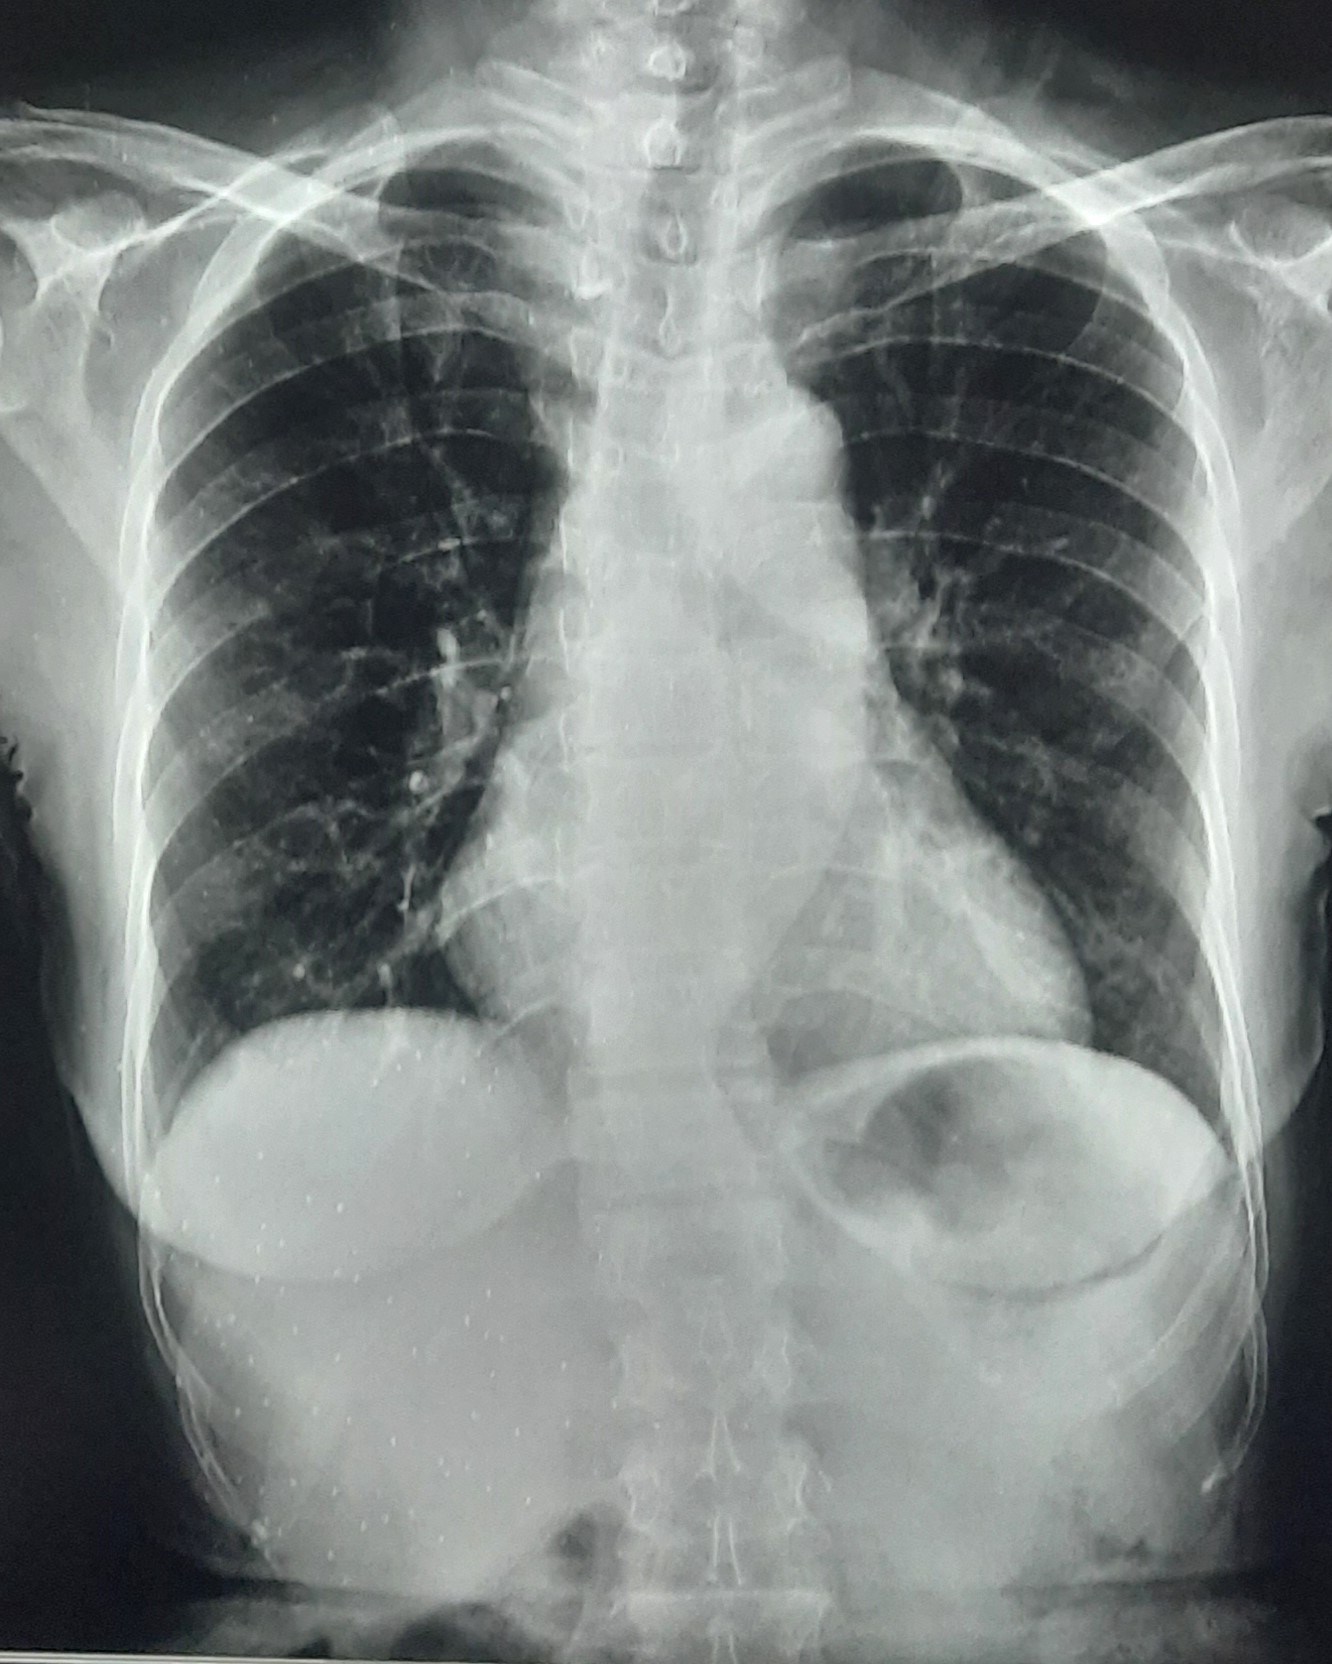

| 340 | IGGMC, Nagpur, Nagpur | P2 | 29-4132 | Ajay Dhabne | Consent taken on Paper | 44 Yrs. |

Provisional Diag : ILD (Interstitial Lung Disease)

Final Diag : ILD In Exacerbation With Old Treated Pulmonary TB With Post Covid Satiation |

Result awaited (Suspected TB/Non-TB) | Abnormality visible on x-ray |